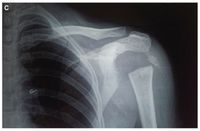

Hasil pemindaian radiografi, beberapa tulang bahu tidak ada. Foto: BMJ Case Reports |

Hasil pemindaian radiografi, beberapa tulang bahu tidak ada. Foto: BMJ Case Reports